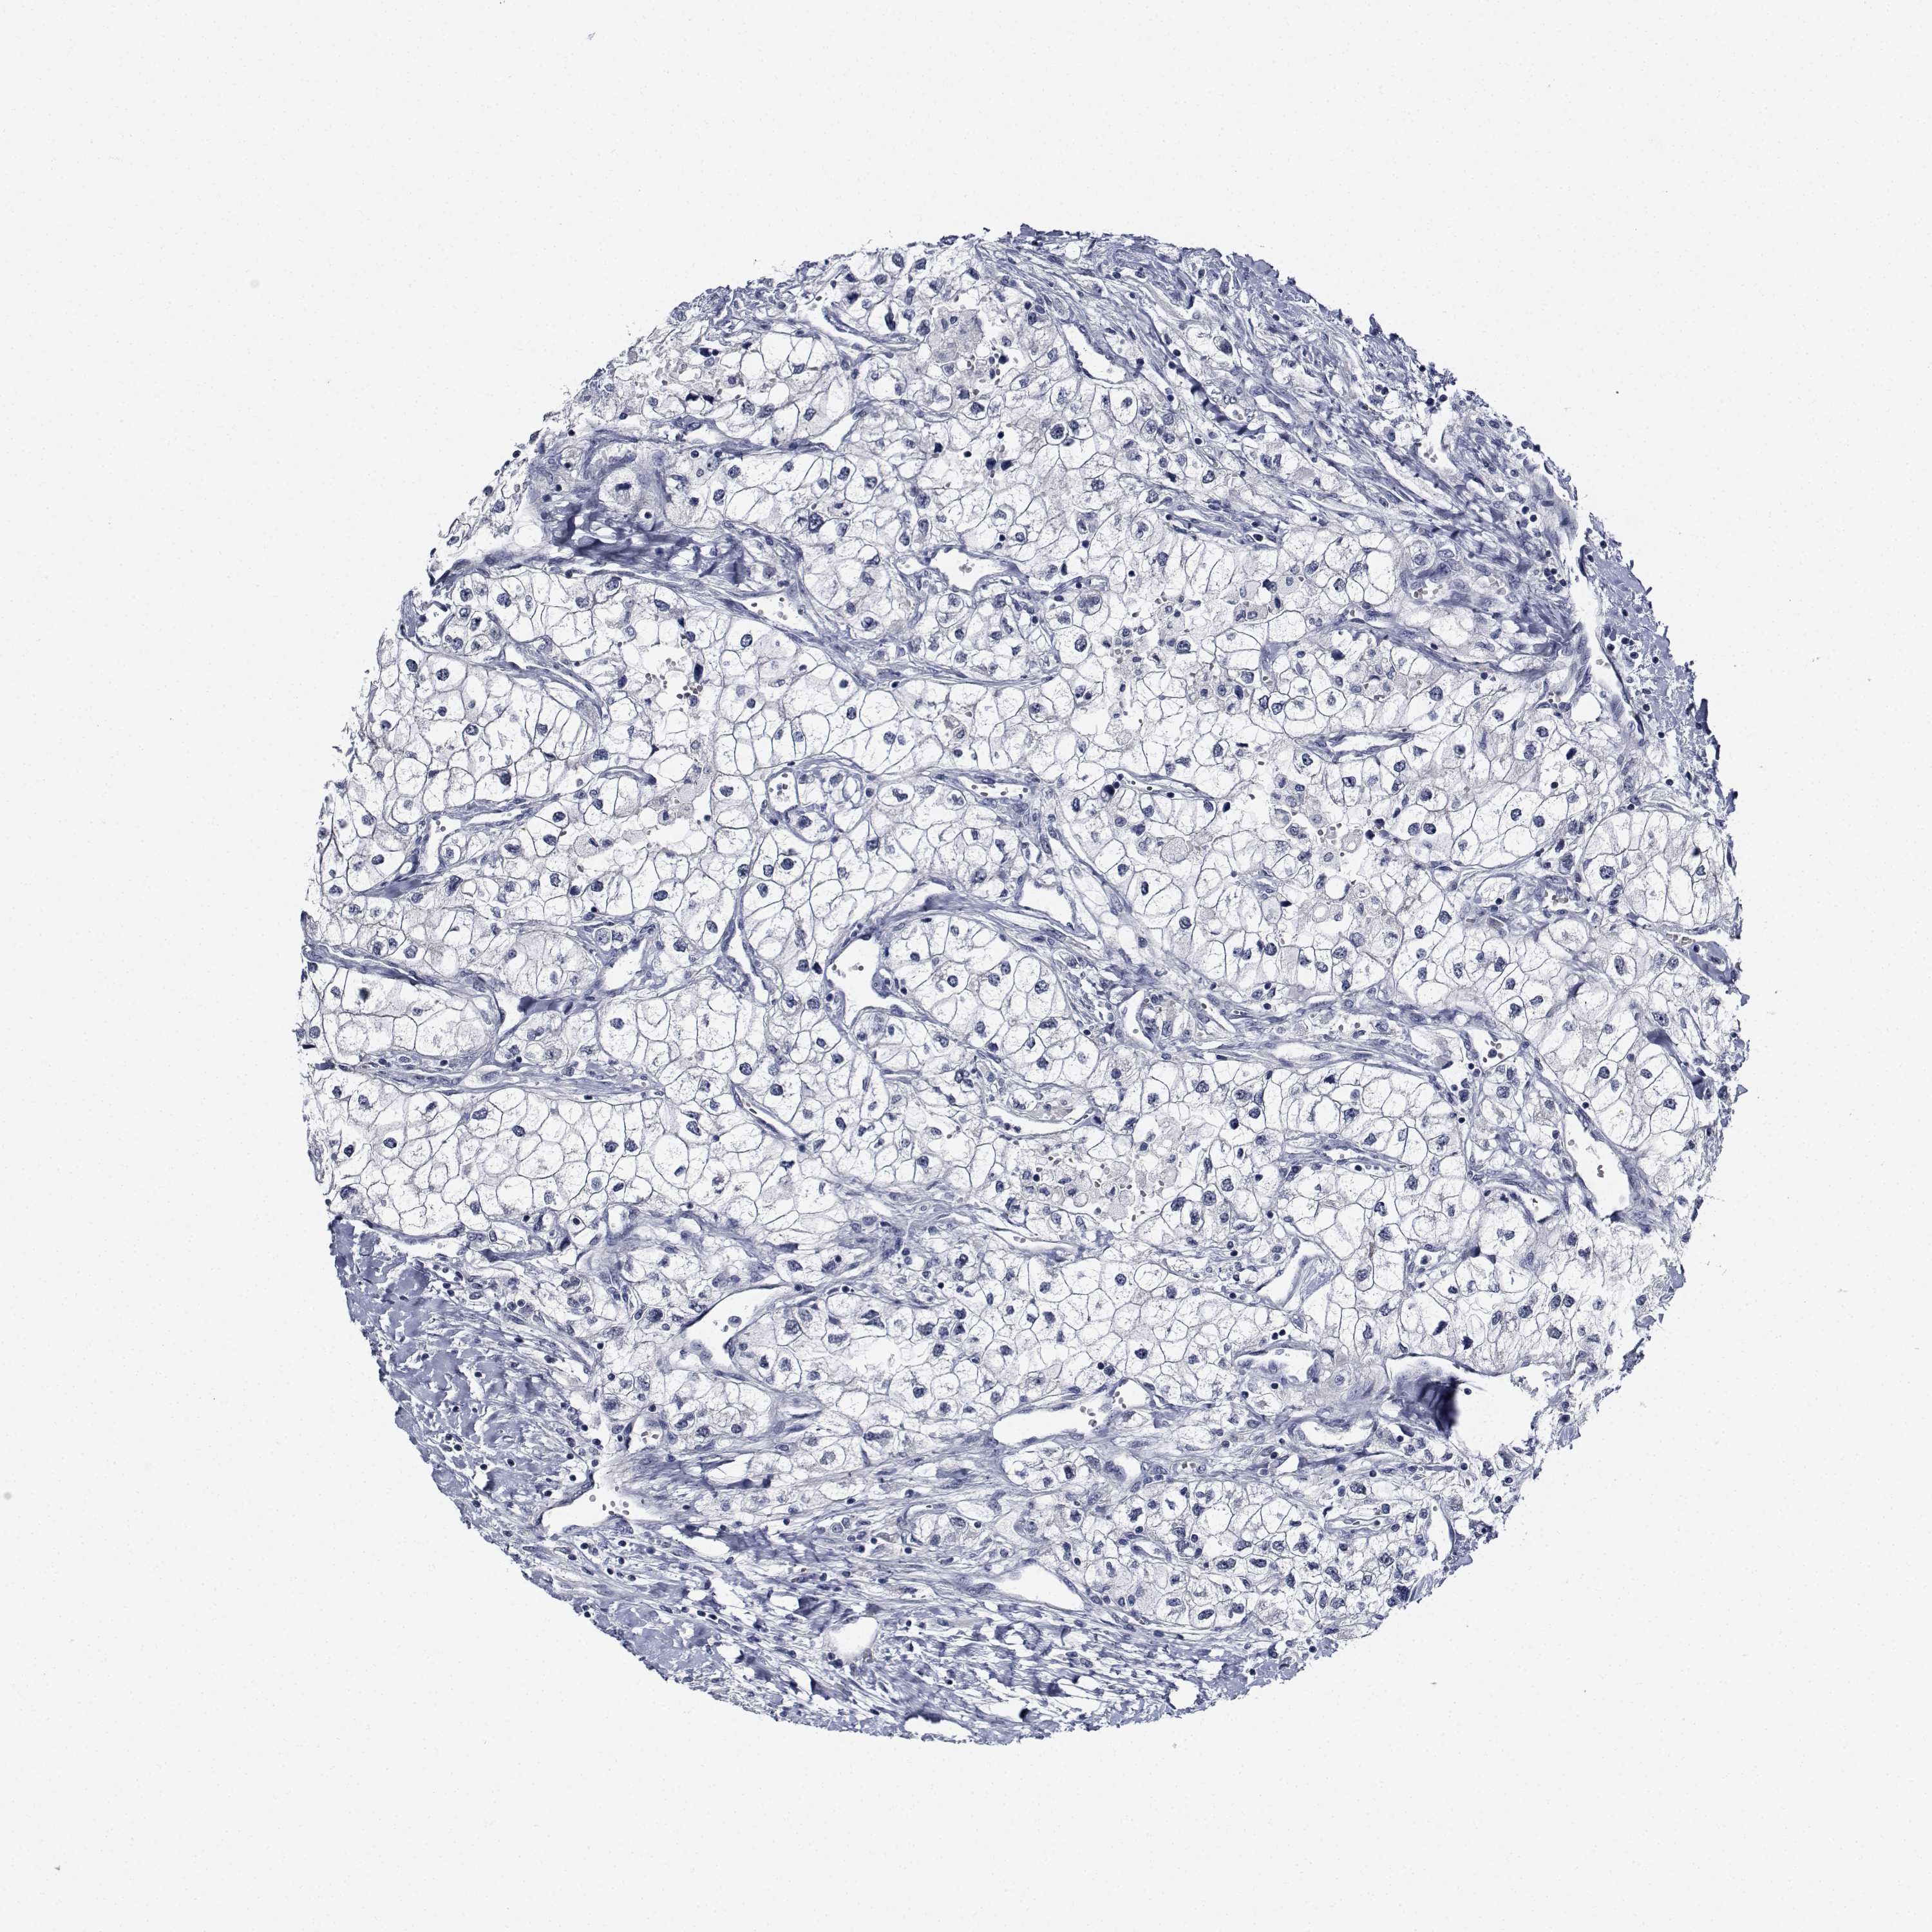

CANCER RENAL CANCER Show tissue menu

KICH TCGA KIRC TCGA KIRC VALIDATION KIRP TCGA PROTEIN RCC CPTAC PROTEIN EXPRESSION